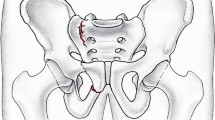

Radiographic results

The SI group showed vertical displacement due to screw penetration through the cancellous bone. In the TITS group radiographic vertical displacement was less and a bending of the screw was seen in all cases (Fig. 5).